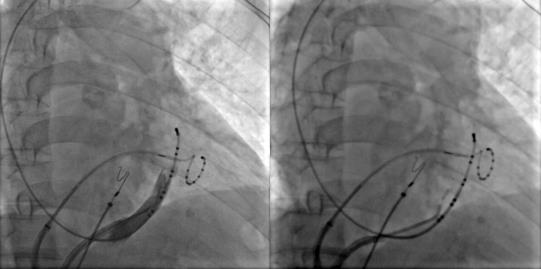

冠狀竇造影定位Marshall靜脈,應(yīng)用OTW球囊進(jìn)行酒精消融

Marshall靜脈酒精消融完成后進(jìn)行左房標(biāo)測(cè)提示二尖瓣峽部徹底隔離,酒精消融成功,接著進(jìn)行三尖瓣峽部消融后患者房撲轉(zhuǎn)為竇性心律,完美完成此次房顫的消融手術(shù)。